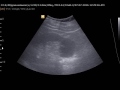

При первых признаках перелома, таких как сильная боль, ослабленная возможность движения и отек, следует немедленно обратиться в больницу или к врачу травматологу для получения помощи. Врач проведет необходимые исследования и рентген, чтобы определить степень повреждения пятки и назначить соответствующее лечение.

Переломы пяточной кости

Перелом пяточной кости

Миниинвазивные операции при лечении переломов пяточной кости

Перелом пяточной кости. Как лечить по клиническим рекомендациям?

Стресс- переломы пяточной кости. Блок в пяточно- таранном суставе.